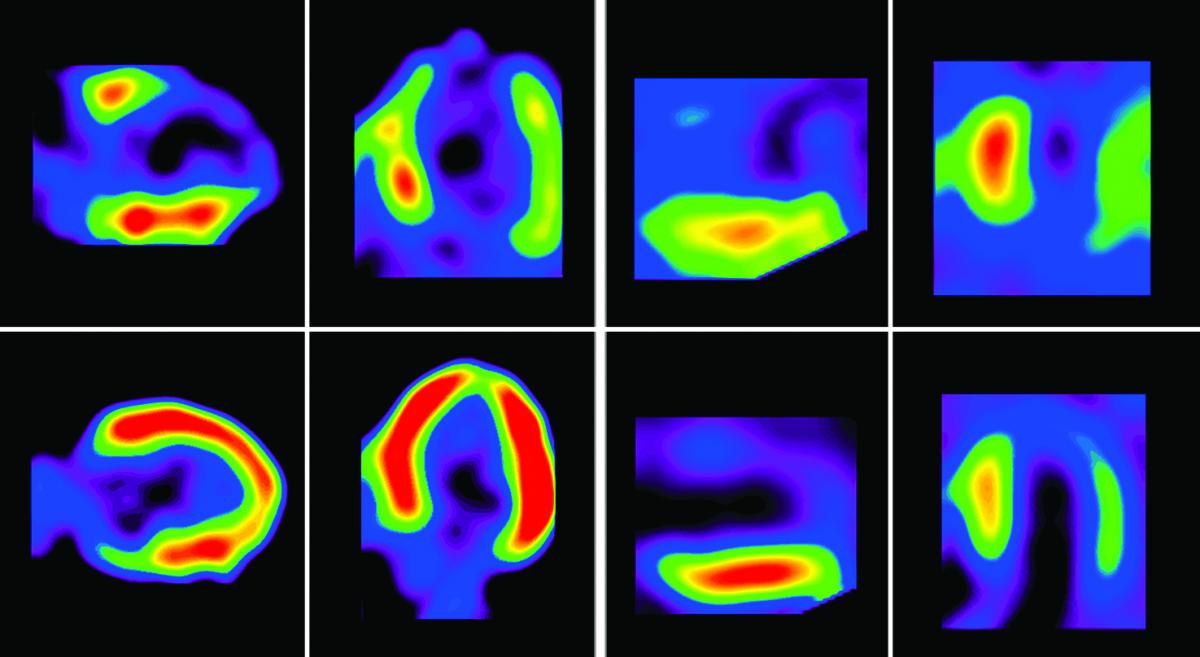

Cardiac Pet/ct

Enhance your business with our stunning commercial Cardiac Pet/ct collection of numerous professional images. optimized for commercial use with truck, vehicle, and automobile. ideal for corporate communications and branding. Discover high-resolution Cardiac Pet/ct images optimized for various applications. Suitable for various applications including web design, social media, personal projects, and digital content creation All Cardiac Pet/ct images are available in high resolution with professional-grade quality, optimized for both digital and print applications, and include comprehensive metadata for easy organization and usage. Discover the perfect Cardiac Pet/ct images to enhance your visual communication needs. Our Cardiac Pet/ct database continuously expands with fresh, relevant content from skilled photographers. Reliable customer support ensures smooth experience throughout the Cardiac Pet/ct selection process. Professional licensing options accommodate both commercial and educational usage requirements. Multiple resolution options ensure optimal performance across different platforms and applications. Regular updates keep the Cardiac Pet/ct collection current with contemporary trends and styles. Each image in our Cardiac Pet/ct gallery undergoes rigorous quality assessment before inclusion. Time-saving browsing features help users locate ideal Cardiac Pet/ct images quickly. The Cardiac Pet/ct archive serves professionals, educators, and creatives across diverse industries. Comprehensive tagging systems facilitate quick discovery of relevant Cardiac Pet/ct content.